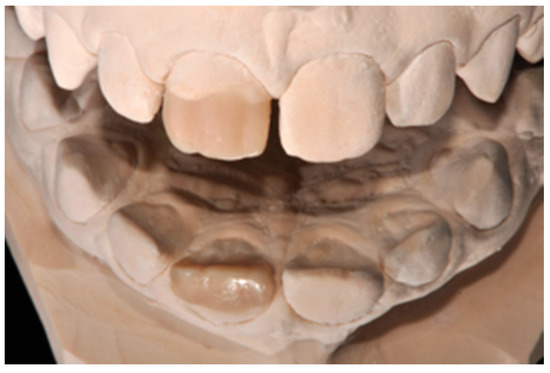

Figure 3.

Wax-up. Reprinted from Restauri diretti nei settori anteriori, G. Paolone, S. Scolavino, © 2021, with permission from Quintessence Publishing Italy.